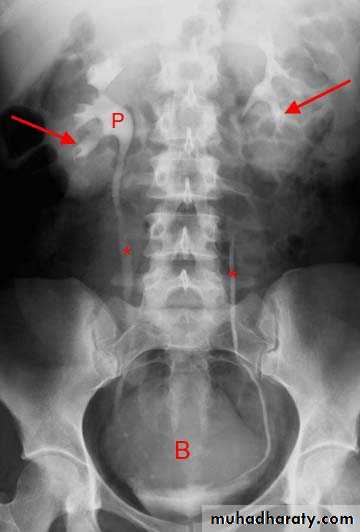

A. First a plain x-ray of the abdomen is taken before the injection of the contrast media, also known as A KUB (kidney, Ureter and Bladder). Calcification & stones may be obscured & missed by contrast media if plain film not takenfirst .

1.Nephrogram phase (Immediately after injection of contrast) .

2. Pyelogram Phase(l-5 minutes after injection of contrast) .